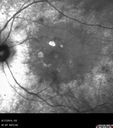

78 year old man: 20/32 OD and 20/50 OS - RP1 Gene is Bad -- > RP with Novel Amino Acid Change in GLY723Stop sequence of the RP1 gene - consistent with AD RP

Retinitis Pigmentosa - RP1 Mutation373 views78 year old man: 20/32 OD and 20/50 OS - RP1 Gene is Bad -- > RP with Novel Amino Acid Change in GLY723Stop sequence of the RP1 gene - consistent with AD RP00000